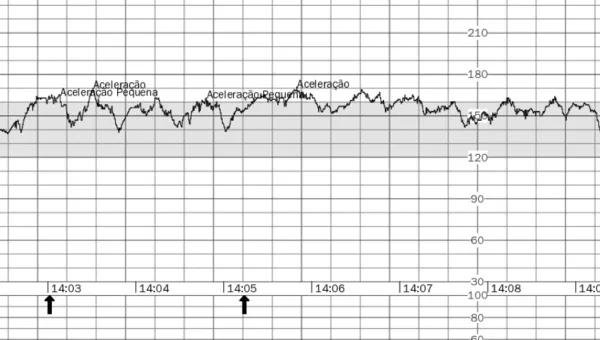

Cardiotocografia Anteparto

Cardiotocografia para monitoramento dos batimentos cardíacos fetais e contrações uterinas. Avaliação do bem-estar fetal em Curitiba.